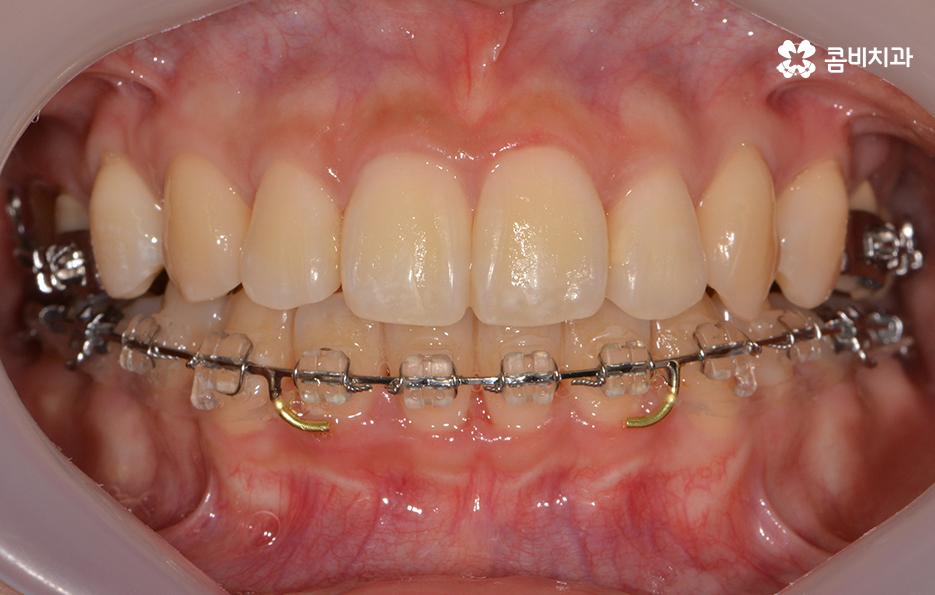

장치를 부착하고 치료의 경과 모습

콤비교정은 평상시 크게 웃지 않는 이상 외부에 시술 사실이

거의 알려지지 않을 정도로 심미성이 우수하기 때문에

직업적인 이유나 성향적으로 교정 장치에 대한 심미적 부담감으로

인해서 망설이셨던 분들에게 많이 선호되고 있는 장치입니다.

윗니가 설측으로 시술이 진행되고 있는 모습이며

발치를 한 부위 안쪽으로 치아가 이동하기 때문에

돌출입의 개선이 함께 이뤄지며 치열뿐 아니라

얼굴과 자연스럽게 어울리는 결과를 얻을 수 있습니다.